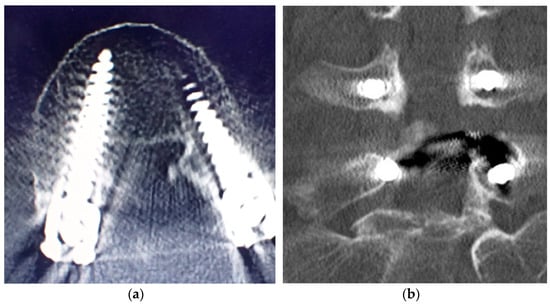

3.4. Adverse Events

In one patient with a grade D breach (Figure 7a,b), screw deviation of the medial pedicle wall with numbness of the right foot developed postoperatively. After reoperation, the symptoms resolved, and no residual neuropathy was observed in this patient. The extra time required for this new procedure was also considered. The extra time was defined from the start of surgery to the completion of intraoperative radiography of the pedicle marker. The average time was 39 min (range: 16–69 min; Table 2) per patient, and patient characteristics had no effect on this result (Table 3).

Figure 7.

(a,b) Computed tomography scan of the screw deviation to the medial pedicle wall in grade D breach.

There are two issues that still need to be considered. The first is the medial deviation of the pedicle of the screw in one of the cases with a Grade D result. This case was a patient with strong osteophyte changes in the facet joints with ossification of the posterior longitudinal ligament of the lumbar spine (Figure 8).